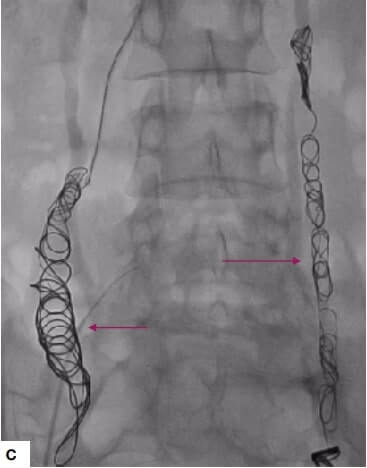

The USG and Doppler images demonstrated pelvic varicosities. The DSA image demonstrated dilated left ovarian vein with reflux into pelvic varicosities and endovascular coiling of ovarian veins. Ovarian vein coil embolization was performed. The postoperative abdominal radiograph demonstrated coils in-situ in bilateral ovarian veins. The patient had recovered and was free from pain at the time of follow up.